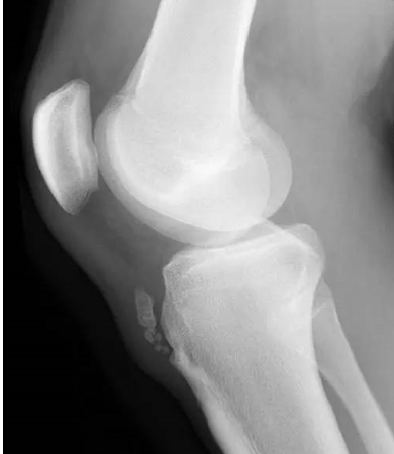

sgood认为这是胫骨结节的不完全撕脱骨折。他指出,胫骨结节一般由胫骨骨干前方的骨骺形成的舌状突起发育而来,少数情况下有一单独的骨化中心,这个骨化中心会发育成独立的骨骺,日后与其上端胫骨的骨骺融合。髌韧带的下端附着于舌状突起,或者单独的骨化中心。突然的伸膝动作会使股四头肌猛然收缩,牵拉力首先通过髌韧带传到胫骨结节,再到达股四头肌腱向外延伸的部分。在典型的胫骨结节撕脱骨折中,可以观察到这些副肌腱与胫骨结节、髌韧带一起从附着点上撕裂下来。这种牵拉损伤多发生于青春期男性,此时骨骺生长最快,胫骨骨干和骨骺间有一层软骨。运动中突然的暴力伸膝,或屈膝状态下摔倒都会引起引起髌韧带突然牵拉胫骨结节而导致胫骨结节损伤。而此胫骨结节骨骺尚未融合,使发生不撕脱骨折。

胫骨粗隆骨软骨病发生于骨骺未闭合前的青年生长期,该处的血循环来自髌韧带,而股四头肌发育较快,肌肉收缩使髌韧带的胫骨结节附着处张力增高并肿胀,引起胫骨结节骨软骨炎。剧烈运动或外伤可导致胫骨结节积累性劳损甚至发生撕脱骨折,从而影响血循环,造成骨骺的缺血性坏死。

由于成纤维细胞的分化和成骨细胞的活跃增生,髌韧带及其附近的软组织可出现骨化,并有新生小骨出现,位于胫骨结节的前上方。这些新生小骨的组织学表现与骨化性肌炎的骨化组织完全相同。由于髌韧带的牵拉,胫骨结节处的成骨细胞活动,促进骨质增生,使胫骨结节增大,明显向前突出。

骨骺完全骨化后,疼痛可消失。检查可发现髌腱肥厚,在髌韧带附着处有增厚和肿胀,胫骨结节增大、隆起、坚硬,压痛明显,膝关节无积液,无压痛,无滑膜增厚。成年后,遗留1个无症状的隆凸,偶尔在髌韧带处有1个疼痛的小骨片,或形成高位髌骨。